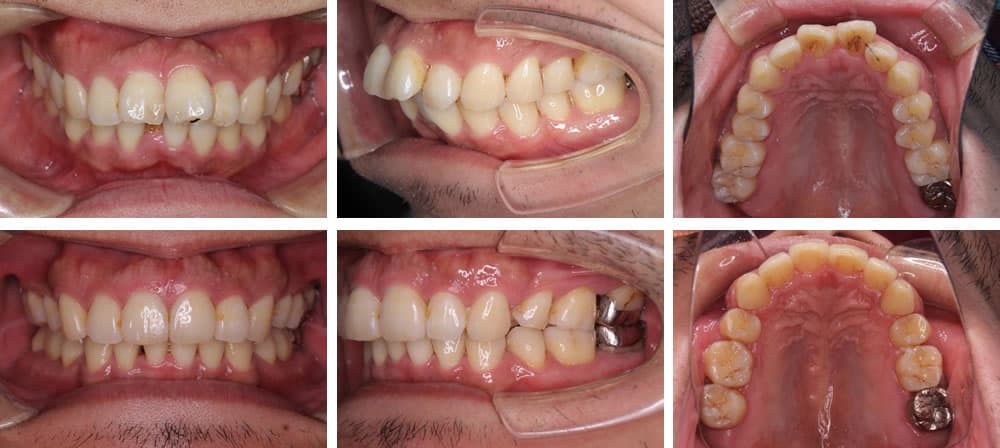

上顎前突(出っ歯)

上顎前突は上の顎や歯が前方に出ている状態の歯並びです。口腔内が乾燥しやすいため、唾液の殺菌作用が低下し、虫歯や歯周病リスクが高くなります。また、見た目が悪いことや前歯を損傷しやすいことも特徴です。